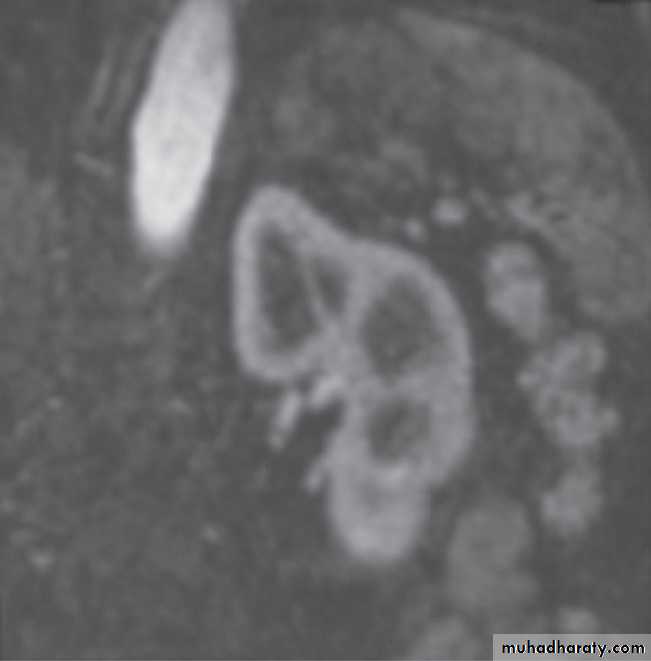

Computed tomography urography

CT is initially performed without intravnous contrast medium (non-contrast CT or ‘CT KUB’) to identify calcification .indication and include:

(i) The early renal cortical enhancement phase.(ii) The homogeneous nephrogramphase; and

(iii)The delayed urographic phase, obtained

several minutes later to demonstrate

contrast within the collecting systems.